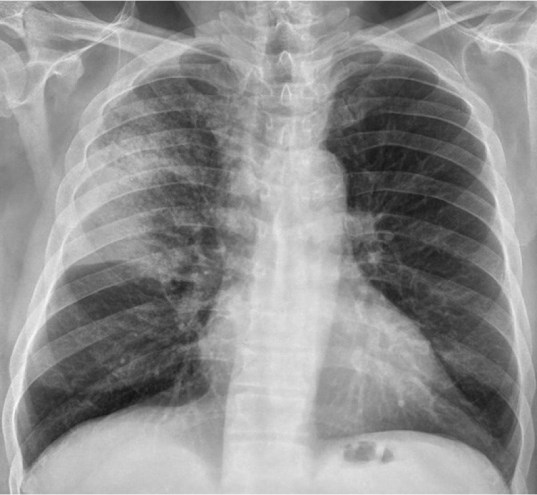

Solución: Es un estudio Normal. Silueta cardiomediastínica y parénquimas pulmonares sin alteraciones significativas.